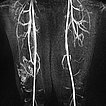

Dynamic MR angiography 62 s after injection of the contrast agent shows slow pooling of the contrast agent in the lesion without early venous return (slow-flow malformation). The lesion is connected to the deep conducting vein system (communicating veins).